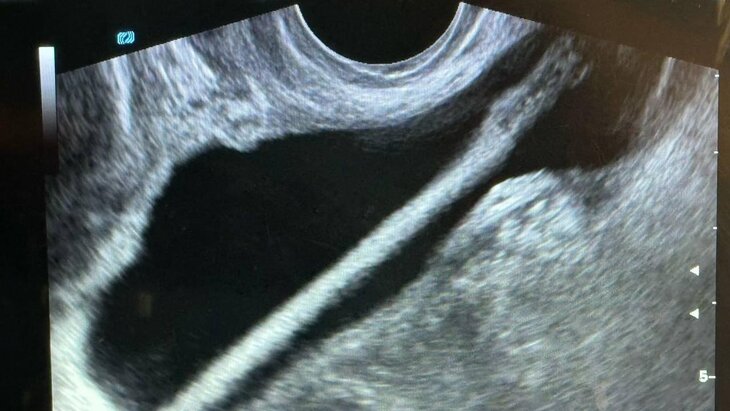

Врачи Красногорской больницы спасли 46-летнюю пациентку, достав из ее мочевого пузыря косметический карандаш, сообщила пресс-служба Минздрава Московской области.

По данным ведомства, в больнице женщина рассказала, что ввела косметический карандаш через мочеиспускательный канал самостоятельно. Так он оказался в мочевом пузыре. Пациентку экстренно госпитализировали в урологическое отделение.

Как рассказал заведующий отделением Петр Сысоев, после УЗИ женщине провели эндоскопическую операцию, в ходе которой инородный предмет успешно извлекли без осложнений. В настоящее время она уже выписана домой.